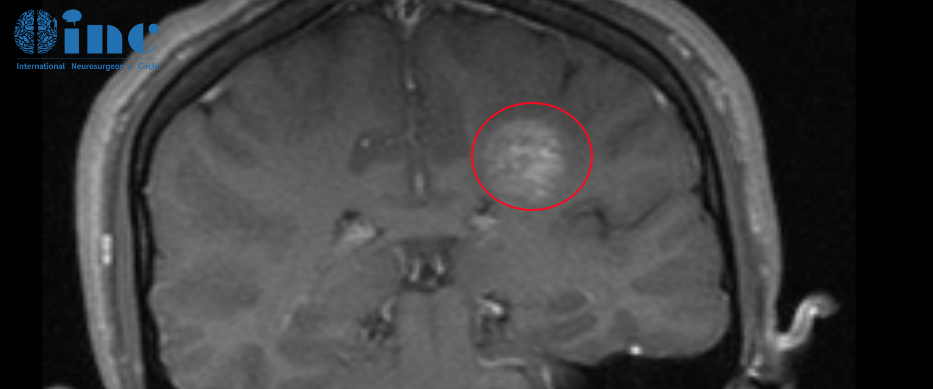

2022年5月,就医检查MRI显示左侧半卵圆中心区可见类圆形异常信号灶大小约8.0x11.0mm。怀疑海绵状血管瘤。

2022年5月MRI影像,血管畸形处于急性出血期

半圆卵中心靠近重要的脑功能区,一旦海绵状血管瘤出血,可能就会对脑功能区造成伤害,影响他的运动、语言等功能。而且这个手术是在深皮质脊髓束区域切除这个海绵状血管瘤!